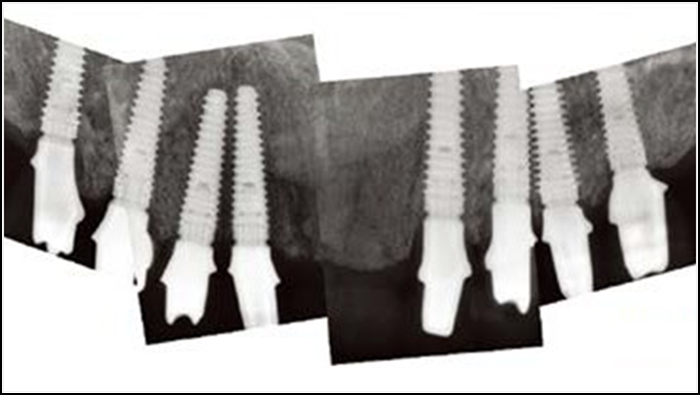

Clinical case: Advantage of fuse abutment with AnyRidge implant for immediate loading in

upper fully edentulous case

- Courtesy of Dr. Kwang Bum Park -

“AnyRidge shows excellent esthetic results

with Zirconia prosthesis in full-mouth rehabilitation case . ”

“AnyRidge shows excellent initial stability

& stable results after immediate loading in

upper fully edentulous case. ”